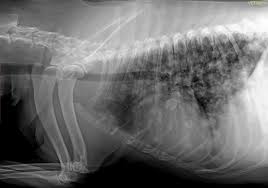

In the beginning stages, many dogs show no clinical signs. Pulmonary adenocarcinoma is cancer of the lungs, which can be primary (originates in the lungs) or secondary (originates somewhere else in the body), is a serious disease that can be fatal if not found and treated early. Metastic neoplasia (cancer) in dogs. That said, here are some general signs and symptoms that indicate the possibility of lung cancer: Almost 70% of dogs with lung cancer experience metastasis to other parts of the lung, meaning treatment may only prolong their life rather than eliminating the disease completely. However, some dogs only experience weight loss (despite a good appetite) and/or lack of energy. Metastatic lung tumors are tumors originating from a cancer elsewhere in the body which has spread to the pet's lungs. Symptoms of lung cancer in dogs usually there are no symptoms in the early stages of canine lung cancer. As the cancer grows, dogs may develop a cough, difficulty breathing, and other symptoms. Lung tumors are relatively rare in dogs, accounting for only 1% of all cancers diagnosed. Life expectancy of a dog with lung cancer. The protocol will often differ based on the symptoms your dog presents with. Computed tomography (ct scan) can be performed to identify some of these lung tumors.

Life Expectancy Of Dog With Metastatic Lung Cancer from media.springernature.com It is estimated that 25% of dogs with a lung tumor show no related signs of cancer. Computed tomography (ct scan) can be performed to identify some of these lung tumors. The dog is not coughing up mucus) although the cough may produce small amounts of phlegm or blood. We have been using prednisone to help with the breathing from the lung tumor, also turkey tail mushroom for the heart tumor, we are also using cbd oil, and just recently added apocaps. Some of the most common ways to test for cancer in dogs include: Symptoms of lung cancer in dogs. Pulmonary adenocarcinoma is cancer of the lungs, which can be primary (originates in the lungs) or secondary (originates somewhere else in the body), is a serious disease that can be fatal if not found and treated early. The second type is metastatic lung cancer whichis cancer that originates elsewhere in the body such as a leg bone, the mouth, or the thyroid gland, but has spread to the lung via the bloodstream.

When it comes to diagnosing cancer in dogs, there are a number of ways to go about this. However, some dogs only experience weight loss (despite a good appetite) and/or lack of energy. Melanomas in dogs tend to affect the mouth and lips, and they can also be found on their nail beds, footpads and eyes. Symptoms of lung cancer in dogs. Lung tumors have moderate to high potential for metastasis (spreading). Life expectancy of a dog with lung cancer. When they do cough, they might bring up blood. Lung tumors are relatively rare in dogs, accounting for only 1% of all cancers diagnosed. The dog may cough up blood, but not mucus. Anonymous we are going through a similar issue. However, some dogs only experience weight loss (despite a good appetite) and/or lack of energy. Lung cancer in pets is rare. Lung cancer in dogs symptoms the symptoms of lung cancer are coughing (which may produce phlegm or blood), exercise intolerance (lethargy), loss of weight or loss of appetite and other respiratory symptoms such as difficulty breathing or shortness of breath.

In general, symptoms develop based on where the metastatic cancer is located, how invasive it is and how long it has been present. In the absence of diagnostic testing, it can be challenging to detect lung cancer in dogs. Cancer of the lungs is a progressive disease, meaning it gets worse over time. That said, here are some general signs and symptoms that indicate the possibility of lung cancer: The dog may cough up blood, but not mucus. At this stage, the tumor can be removed through surgery. The symptoms of metastatic cancer in dogs are not universal. Chronic coughing seems to be the most common abnormality that is seen in dogs with lung cancer. Adenocarcinoma of the lung in dogs. Unlike some other types of cancer, there are some concerning symptoms that arise in the earlier stages of primary lung cancer for dogs that should immediately alert you that something is wrong. Lung cancer in dogs symptoms the symptoms of lung cancer are coughing (which may produce phlegm or blood), exercise intolerance (lethargy), loss of weight or loss of appetite and other respiratory symptoms such as difficulty breathing or shortness of breath. On top of dogs presenting symptoms derived from the primary tumor, in advanced cases, dogs will also show signs of lung cancer. Symptoms of lung metastases pulmonary metastases may not produce symptoms.